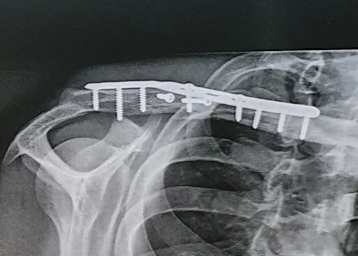

Chris Ponsson (Yamaha): Schlüsselbein war zertrümmertBeim Superbike-Meeting in Misano zog sich Chris Ponsson bei einem Sturz im ersten Lauf einen komplexen Schlüsselbeinbruch zu. Röntgenbilder belegen den desaströsen Zustand der Knochen, die Operation war schwierig.